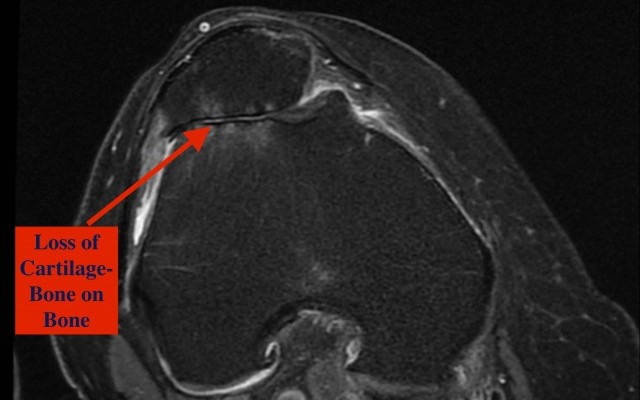

Attached video explains simply what osteoarthritis is and how it manifests as a painful condition.

Many people have knee replacements (also called knee arthroplasty) because they have osteoarthritis. This condition occurs when the cartilage (tissue) that cushions the knee joint wears away. As a result, bone...

Patellofemoral arthritis affects the underside of the patella (kneecap) and the channel-like groove in the femur (thighbone) that the patella rests in. It causes pain in the front of your knee and can make it difficult to kneel, squat, and climb and descend stairs

Patellofemoral arthritis occurs when the articular cartilage along the trochlear groove and on the underside of the patella wears...